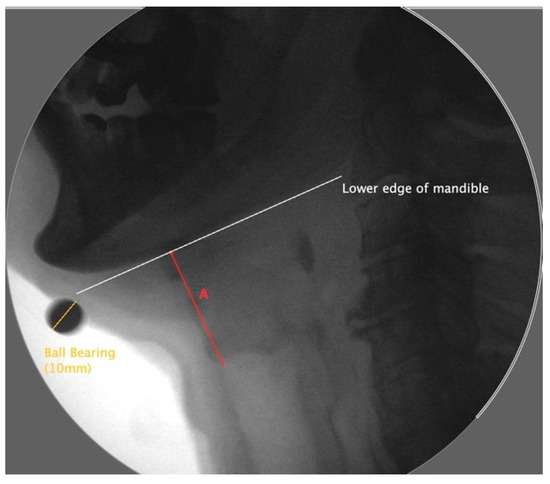

2.4.1. Hyoid Bone Displacement